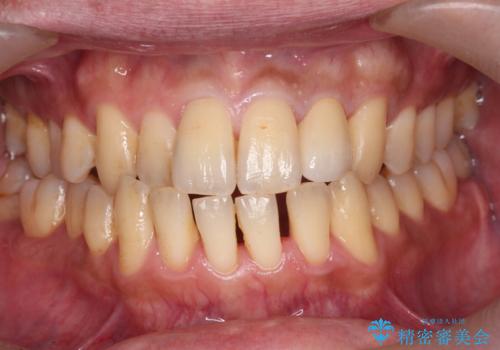

前歯のセラミック治療

- 左の前歯が黒いとのことで来院。

1番目の歯は小さい虫歯があったのでプラスチックの樹脂で治療をしました(保険内)。

2番目の歯は二箇所虫歯があり、プラスチックの樹脂で治療するとつぎはぎみたいになってしまうので、

白い被せ物(ジルコニアクラウン)で治療しました。

自然な被せ物が入り、大変満足して頂けました。